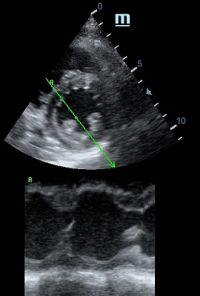

Но как же провести стандартные измерения в М-режиме, если мы его не использовали? На помощь приходит функция Free Xros M – анатомический М-режим. Имея записанную в память прибора видео петлю, мы можем провести линию М-режима в любом месте, при этом корректируя изначально не оптимальный угол.

MAPSE - амплитуда движения латерального кольца митрального клапана, позволяет рассчитать фракцию выброса по формуле EF = 4.8 × MAPSE (mm) + 5.8, очень быстрый и гораздо более точный («прародитель Strain») метод чем широко распространенный метод Teicholtz. В современных приборах можно легко добавить свою формулу при отсутствии ее в стандартном калькуляторе. Главным условием является проведение линии М-режима параллельно стенке левого желудочка в апикальном четырехкамерном сечении, что легко достигается при использовании функции Free Xros.